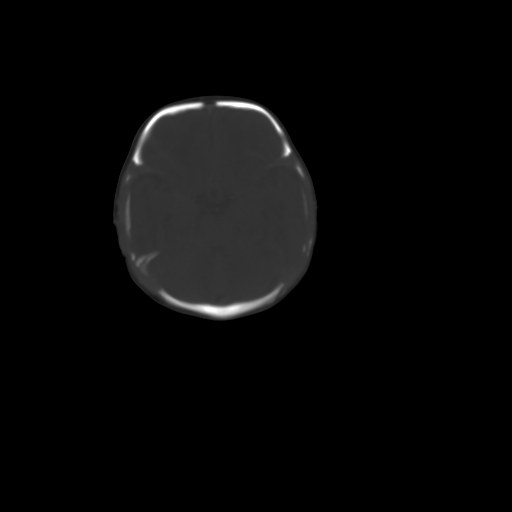

男,12天,自然分娩,其母发现右顶部头皮包块逐渐增大。

右顶部头皮血肿

右顶部头颅血肿(骨膜下血肿)

右顶骨呈膨胀性改变,骨纤维结构不良?

右顶部头皮血肿,可能是产道挤压所致。以后会慢慢恢复。

鉴别:骨膜下血肿,一般为产伤,应用产钳之类的吧